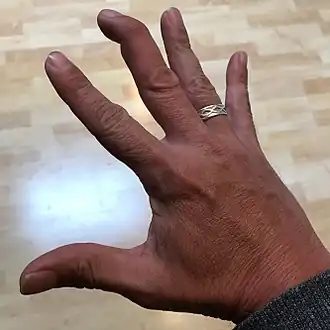

| Mallet finger of the middle finger. The tip of the finger bends downwards while the other fingers stay straight. | |